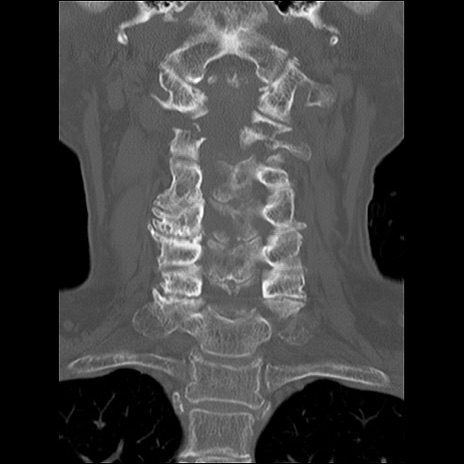

症例48 頚椎CT(冠状断像)

頚椎CT